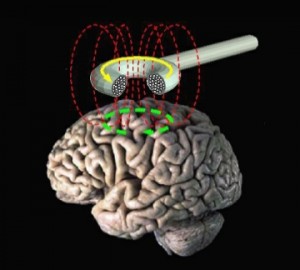

La tecnica si basa sul principio dell’induzione elettromagnetica e prevede la creazione di un campo magnetico allo scopo di eccitare i neuroni attraverso l’uso di un casco (realizzato apposta per creare il campo magnetico). Questo casco viene collegato ad un generatore di corrente ad alta intensità e viene collocato sul cranio del paziente per stimolare la corteccia celebrale e le cellule nervose attraverso un impulso magnetico indolore, in una particolare zona del cervello (scelta in base alla “patologia” da trattare).

I metodi usati sono due, il primo è detto Single Pulse TMS (singolo impulso) che prevede una sola scarica e il secondo chiamato Repetitive TMS (impulsi ripetuti) che prevede più scariche in un periodo di tempo definito.